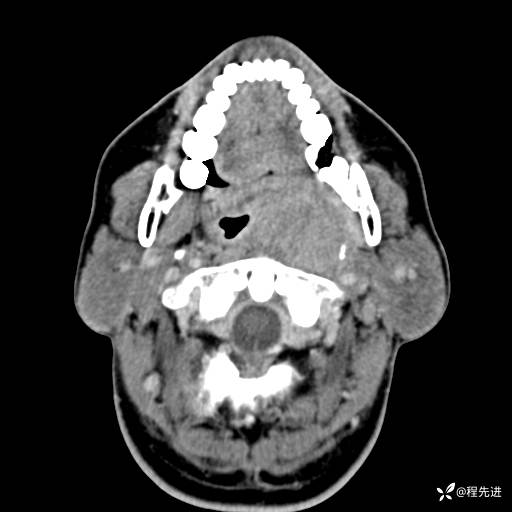

CT平扫:

CT增强:

动脉期: